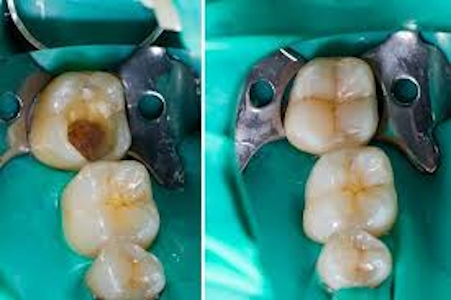

Fillings Fillings are one of the most common restorative treatments, used to repair cavities caused by tooth decay. Dentists remove the decayed portion of the tooth and fill the space with materials such as composite resin, amalgam, gold, or ceramic. Composite fillings are particularly popular as they blend seamlessly with natural teeth.